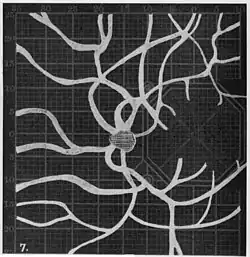

Angioscotomas were first discovered and mapped out by John Norris Evans (1891-02-28--1953-04-08)[2] in 1926, who coined the term angioscotometry to describe the painstaking charting of the scotoma of the retinal blood vessels by manual perimetry. He seated each subject in a seat in a dark setting, and tested whether they could see a tiny bright test object placed at various locations.[3] Using a 1.5 mm white disk, Evans reported intricate branch‑like scotomas that mirrored the arteries and veins emerging from the optic disc, with a full map requiring up to 2 hours to complete. He plotted this for subjects under various conditions, such as while holding breath, with glaucoma, etc. A year later, he confirmed that only short stump‑like scotomas had been noticed previously, some further data plotted with a smaller 1 mm stimuli, and under varying conditions on the subject.[4] He published a monograph on this in 1938 in which he described its use in assisting diagnosis of various conditions, such as retinal edema, glaucoma, optic neuritis, etc.[5]

1. Pressure on globe shows only stumps of large vessels. 2. Holding the breath causes similar effect; also 3. Holding the head low. 4. Pressure on opposite eye widens arteries and still more veins, 5. Pressure on the carotid produces no definite effect. 6. Looking thru red glass brings out finer vessels. -

Widening of angioscotoma under various conditions (holding head lower than trunk; holding the breath; making digital pressure on the same eye; (a vein) on opposite eye; (an artery) on opposite eye).